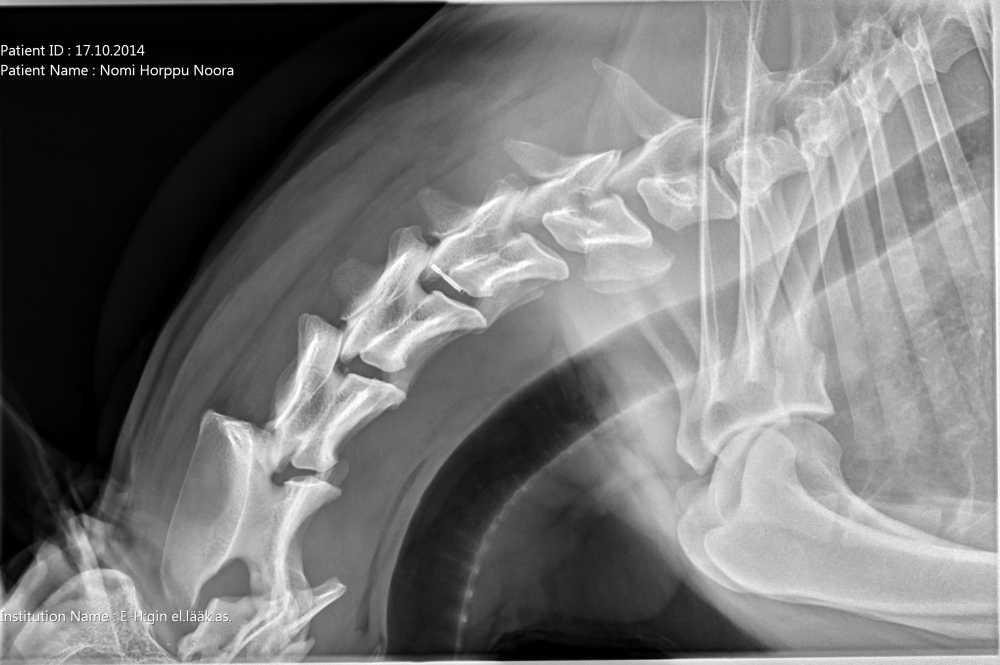

Quti viety lääkäriin, koska vingahtelee kääntäessän päätään. Koko selkä kuvattiin, ei muutoksia. Oireiden jatkuessa kaularanka

magneettikuvattiin. Kuvanneen eläinlääkärin mielestä Nomilla on välilevyrappeuma ja kaikki harrastaminen mietittävä uudelleen.

Halusimme toisen mielipiteen Timo Talviolta, joka halusi ottaa Nomin kaularangasta taivutuskuvat. Talvion mukaan kyseessä ei ole

välilevyrappeuma vaan taivutuskuvissa näkyy kaularangan nikamien 5 ja 6 välillä liukuma. Lääkekuurin ja levon jälkeen voi

harrastamista jatkaa normaalisti. Talvion lausunto:"Kyse on nikamien välisestä "löysyydestä". Selkärangan rakenteelliset

viat ovat pääsäänöisesti perinnöllisiä, mutta tällainen lievä nikamien välinen liikkuvuus ei sellaisenaan ole perinnöllistä,

toki perintötekijät voivat altistaa tämänkaltaisen tilan kehittymiseen."